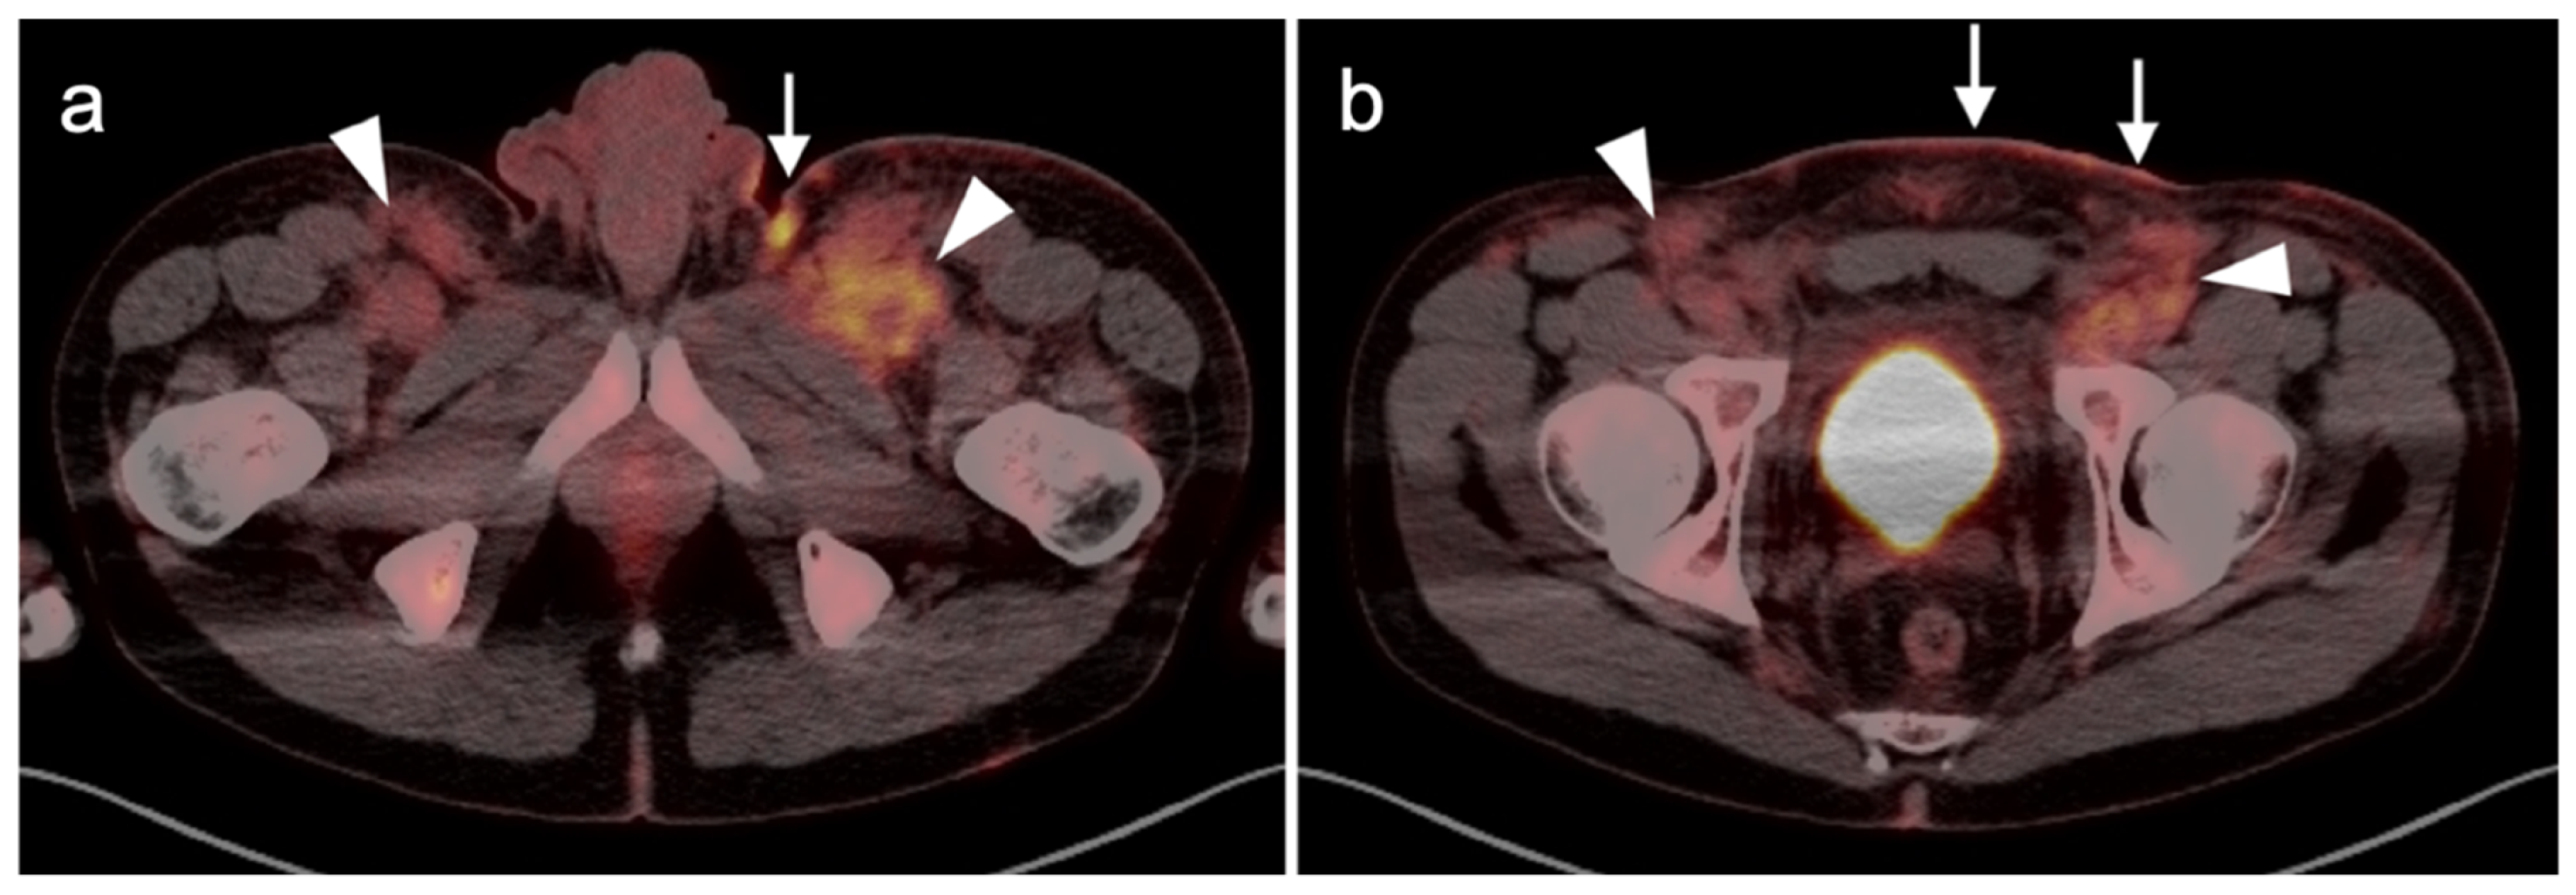

3.1.5. Rhabdomyosarcoma

- Mercolini, F.; Zucchetta, P.; Jehanno, N.; Corradini, N.; Van Rijn, R.R.; Rogers, T.; Cameron, A.; Scarzello, G.; Coppadoro, B.; Minard-Colin, V.; et al. Role of 18F-FDG-PET/CT in the staging of metastatic rhabdomyosarcoma: A report from the European paediatric Soft tissue sarcoma Study Group. Eur. J. Cancer 2021, 155, 155–162. [Google Scholar] [CrossRef]

- Tateishi, U.; Hosono, A.; Makimoto, A.; Nakamoto, Y.; Kaneta, T.; Fukuda, H.; Murakami, K.; Terauchi, T.; Suga, T.; Inoue, T.; et al. Comparative study of FDG PET/CT and conventional imaging in the staging of rhabdomyosarcoma. Ann. Nucl. Med. 2009, 23, 155–161. [Google Scholar] [CrossRef]

- Donner, D.; Feraco, P.; Meneghello, L.; Rombi, B.; Picori, L.; Chierichetti, F. Usefulness of 18f-FDG PET-CT in Staging, Restaging, and Response Assessment in Pediatric Rhabdomyosarcoma. Diagnostics 2020, 10, 1112. [Google Scholar] [CrossRef]